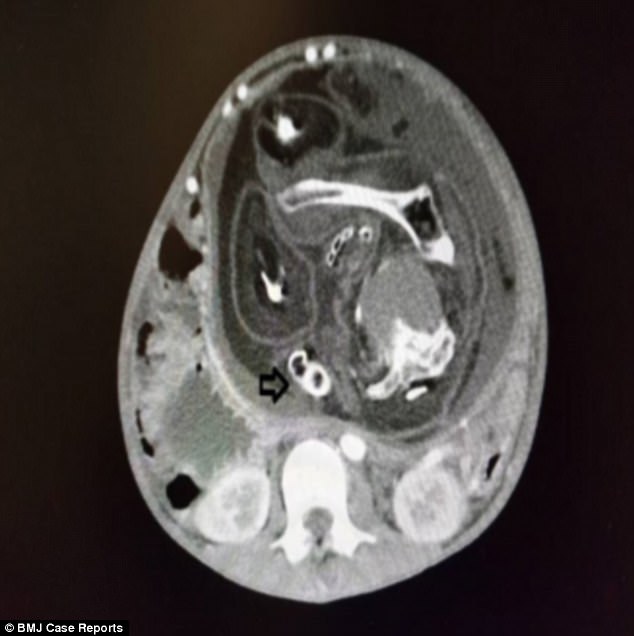

Seperti yang dikutip dari tribunjatim.com, CT Scan pun dilakukan terhadap perut si bocah laki-laki ini.

Setelah dilakukan pemeriksaan akhirnya terungkap, jika tonjolan keras yang terasa di bagian perutnya itu adalah sebuah janin.

Kasus satu ini sampai dimasukkan ke dalam BMJ atau British Medical Journal terkait kehebohan yang ditimbulkan dari kasus satu ini.

Janin itu memiliki berat sekitar 1,6 kg dan memiliki tubuh yang cacat.

Janin itu memiliki panjang 23,8 sentimeter.

Janin cacat itu memiliki rambut panjang, alat kelamin pria dan juga kulit.

Tidak memiliki mulut, tapi pusar atau plasenta.

Dalam dunia medis dikenal dengan fetus in fetu. Kondisi ini memang tergolong langka.

Fetus in fetu, yaitu kondisi di mana salah satu janin anak kembar malah tumbuh di dalam tubuh janin kembarannya.

Kondisi ini bisa terjadi pada tahap awal kehamilan kembar. Janin masuk melalui tali pusat dan menjadi parasit yang hidup di tubuh saudara kembarnya.